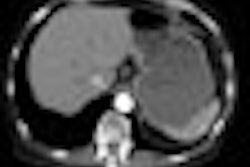

To accomplish these tasks the software automates a number of steps, which are calibrated with a small cross-sectional calcium hydroxyapatite phantom scanned simultaneously with the patient, followed by standardization that employs the patient's pool of blood and muscle in a "hybrid calibration" program. The software in background automatically computes two scoring thresholds, and statistical computations are based on voxel size and image noise.

The software detects and displays the results in a viewable 3D plaque map that shows each plaque in three planes referenced to its exact 3D location in the volume dataset. The benefit of the automation is that a 160-slice image dataset can be scored in approximately three seconds, according to the company.